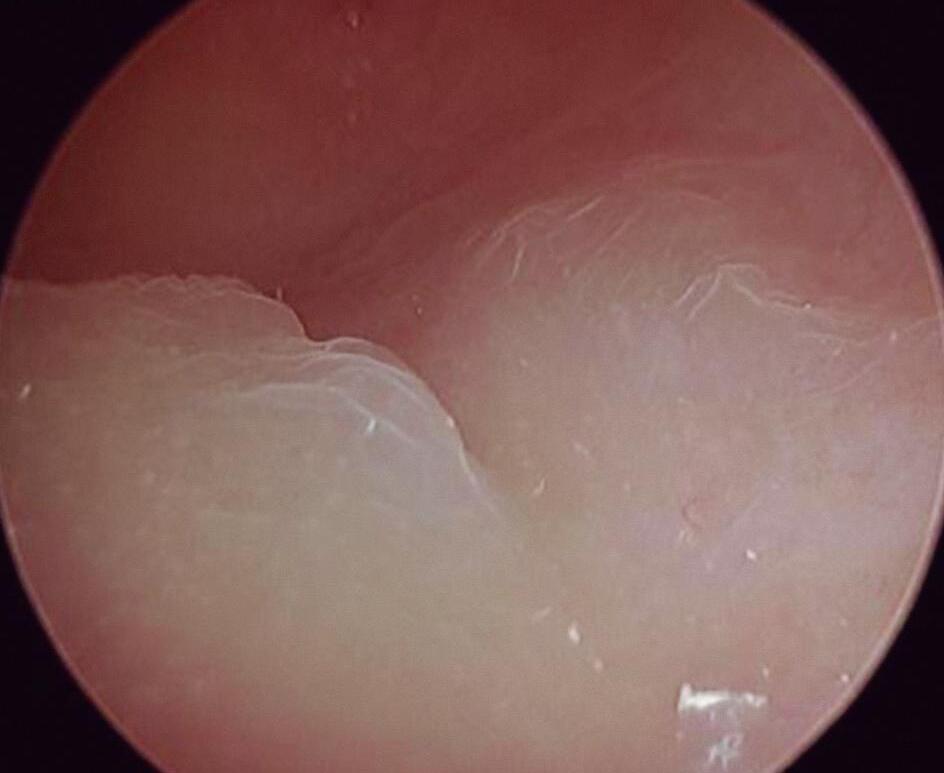

Endométrio Hipotrófico

Nessa fase, a cavidade ainda tem forma e volume normais. Endométrio fino, esbranquiçado, pálido, com glândulas esparsas. Vasos delgados e curtos (Fig. 1-22).